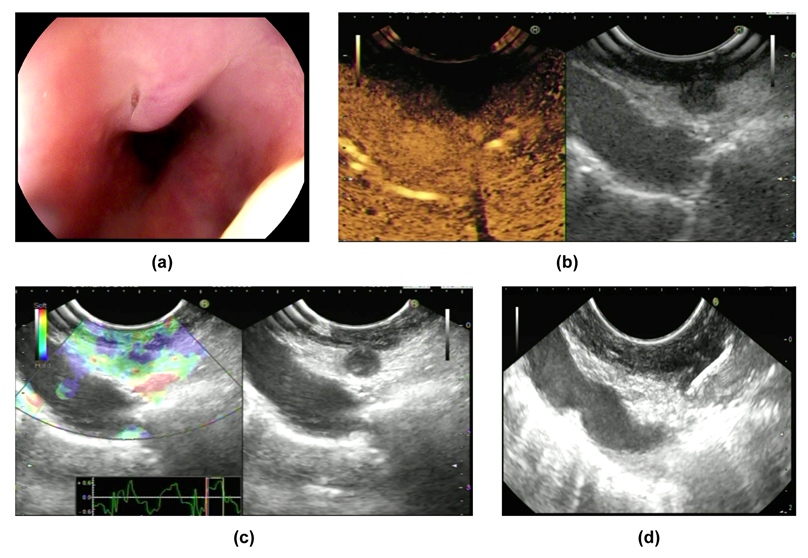

Tuberculous lesions encroach on and result in the formation of an abnormal communication between the esophagus and trachea. A double-barreled appearance can be seen when using endoscopy (Figure 3a,b). Meanwhile, the fistulous opening can be observed near the carina using bronchoscopy. A tracheoesophageal fistula can increase the risk of aspiration pneumonia, as reported previously [5]. This double-barreled appearance may resemble fistula tracts caused by aggressive fungal infection or esophageal carcinoma. Histopathology and pathogeny can be relied on to confirm the diagnosis [35,36].

8. Case Reports

The pathological results discovered granuloma in all patients. PCR and Ziehl-Neelsen staining were performed on two patients, but the results were all negative. Finally, diagnostic anti-tuberculosis therapy was conducted. After 9 months of drug treatment, four patients were asymptomatic. After 1-year follow-up, all of the lesions had disappeared and left scars on the esophageal mucosa according to endoscopy (Figure 3d).

Figure 3. Manifestations of Case 4: (a,b) manifestations of the lesion according to EGD; (c) the lesion as shown by EUS; (d) changes shown by using endoscopy after drug treatment.